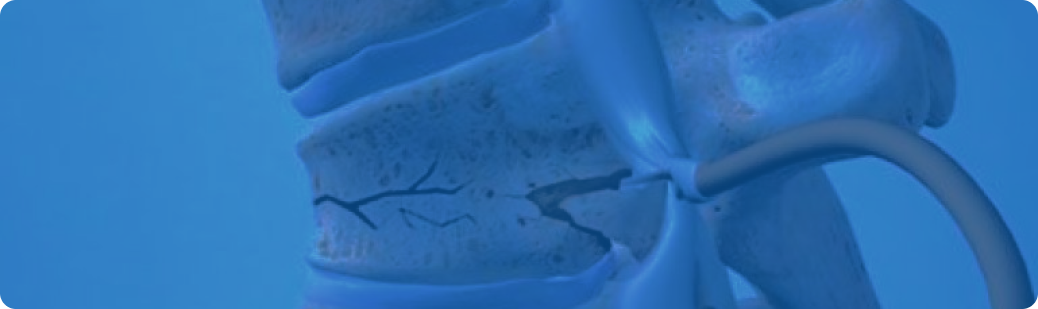

Самым серьёзным осложнением при остеопорозе является компрессионная травма позвоночного столба. До этого момента заболевание чаще всего совершенно не дает о себе знать.

Остеопороз диффузной формы – это тяжелая болезнь костных тканей. При таком заболевании кости истончаются по всему организму, определяется их повышенная хрупкость и пористость. В этом случае повышается вероятность получить перелом любого участка скелета, включая позвоночник.

Если патология находится в запущенной форме, кости могут деформироваться либо ломаться даже при незначительных нагрузках. Кроме того, при подобном заболевании могут появляться трещины в костях.

При диффузной форме заболевания поражены все ткани скелета, из-за этого патология ещё носит название «стеклянная болезнь костей». Патология характеризуется медленным, почти незаметным течением.